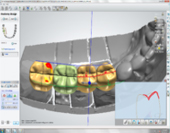

Advanced surgical training and extensive experience in all fields of Dental Implantology, including Bone Grafting, Sinus Lifts and Multiple Dental Implants placements allow Dr. Andrews to complete a surgical phase in one visit in 85% of all cases. Being a world-renowned expert in Digital Dentistry, Dr. Andrews utilizes Digital Implant Planning , Digital Smile Design (DSD) and Guided Implant Placement to achieve unparalleled success. Use of Platelet Rich Plasma/Fibrin, or PRP/PRF, dramatically reduces post-operative discomfort, shortens healing time, accelerates integration of implants & grafts and decreases the likelihood of most complications. CAD/CAM restorative protocols and 3D printing are used for all Implant restorations to be delivered with the highest level of precision.

Dr. Andrews is one of the most advanced CAD/CAM dentists in the world. He uses advanced intraoral digital 3D scanning technology with 10-micron precision (0.0004 inch) which produces a perfect replica for tooth restoration and implant placements…